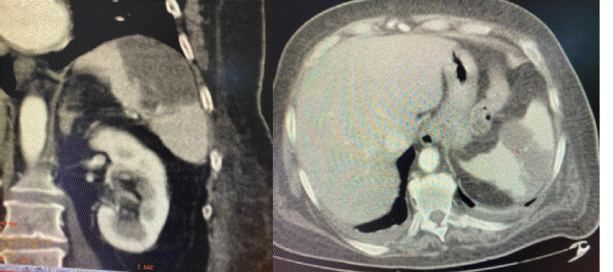

Se realizó ronda de hemocultivos (HC) en tres oportunidades que fueron negativos y ecocardiograma transesofágico (ETE) en dos oportunidades que no mostró vegetaciones o masas. Se completó la valoración en búsqueda de fenómenos embólicos con TC de abdomen que confirmó infartos esplénicos múltiples e infartos renales (figura 3).

Figura 3: Tomografía de abdomen. Se observan lesiones hipodensas múltiples en el bazo y riñón izquierdo compatibles con infartos.